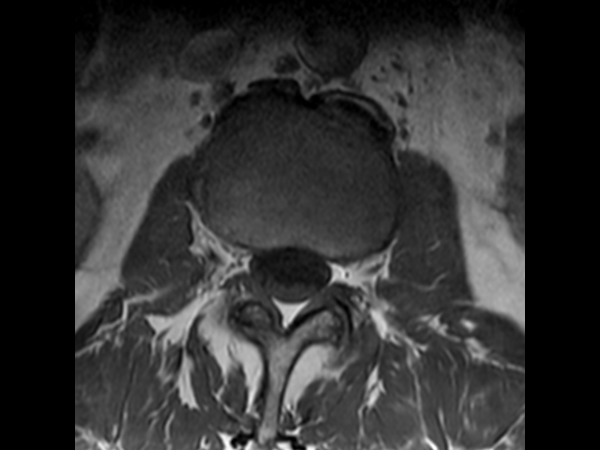

Comprehensive Lumbar Spine imaging at 3.0T